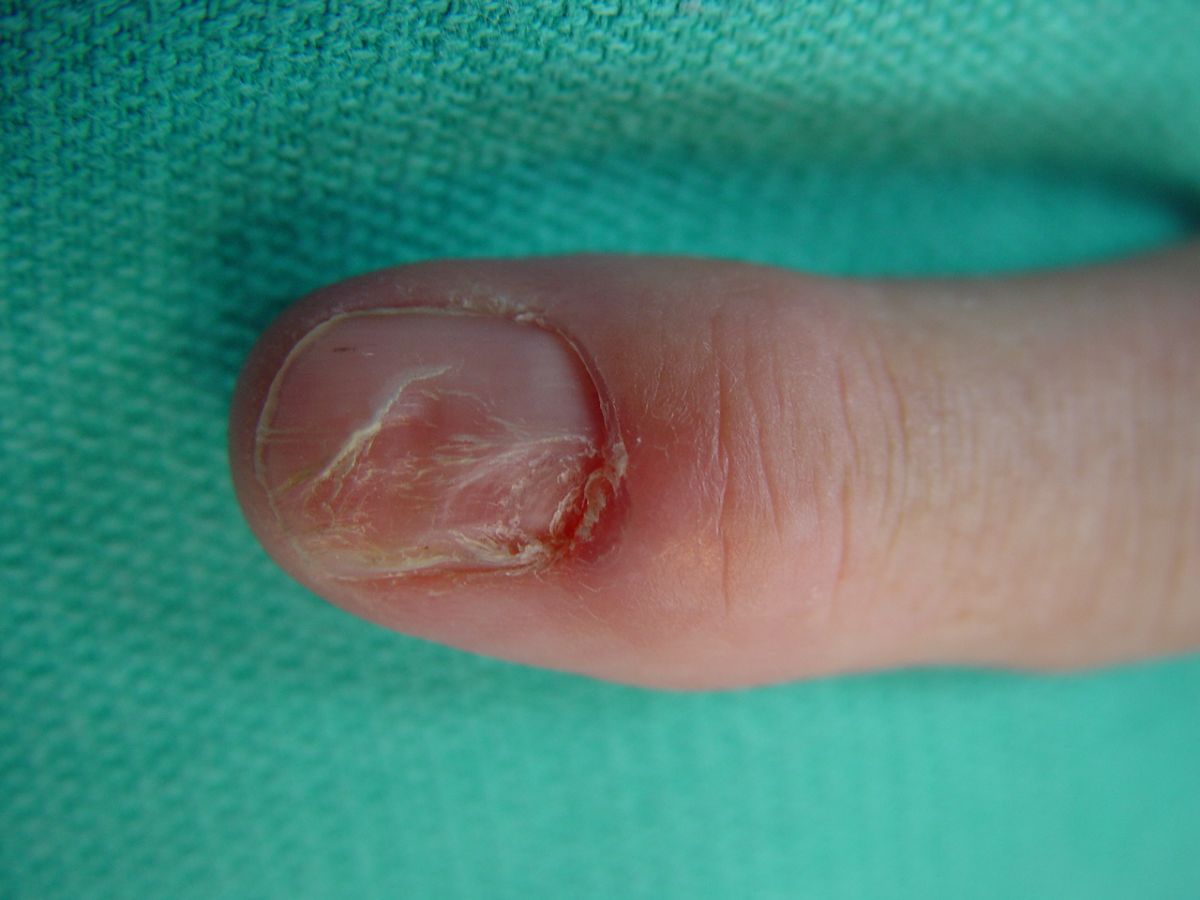

Case 1.

Mucous cyst. Mucous cysts (distal interphalangeal joint synovial cysts; myxoid cysts) commonly result in longitudinal concavity of the nail plate from pressure on the germinal matrix.

Highslide

Typical secondary contour/

These are usually filled with clear colorless gelatinous material with an appearance similar to mucous, but technically is thickened synovial liquid, not mucous. The superficial location allows the diagnosis to be confirmed with transillumination.

Another mucous cyst, more centrally located. Note both the nail deformity and the thin overlying skin. Repeated cyst drainage may lead to joint infection.